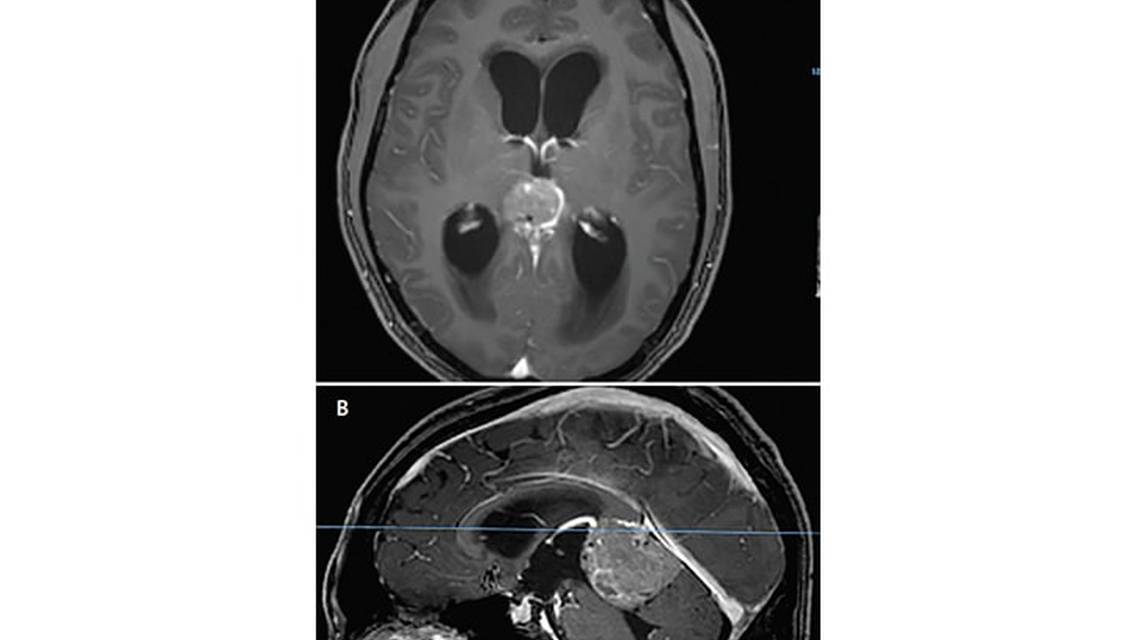

Brain MRI (Figure 1) showed a mass in the pineal region measuring approximately 4 cm at the greatest dimension and causing marked compression on the dorsal midbrain and cerebral aqueduct resulting in obstructive hydrocephalus.